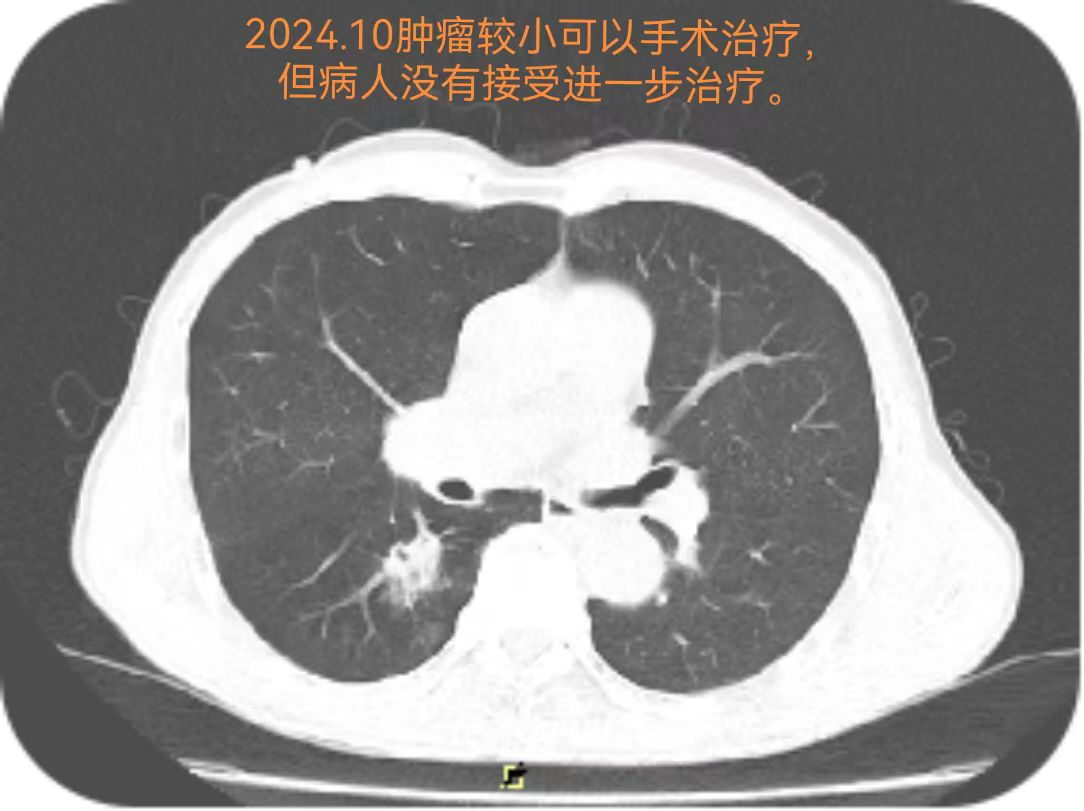

更让人惋惜的是,早在2024年10月,吴伯就已发现肺部异常,却因未积极治疗导致病情加重。这也再次提醒大家:肺部不适及时就医、发现异常尽早干预,对癌症诊疗至关重要。